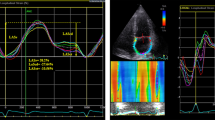

2D-STE image acquisition using the Vivid E9 ultrasound system (GE Healthcare) was performed with apical four-, three-, and two-chamber views to achieve optimal imaging quality for subsequent analyses. EchoPAC software was used to trace the LA endocardial border in both the four- and two- chamber views (LA strain values using the four-chamber view alone were analyzed and presented in the additional file 1), while taking care to exclude the appendage and pulmonary veins from the LA cavity [21]. LA longitudinal strain was calculated as the average LA strain in six segments. LASr, LA conduit strain (LAScd), and LA contraction strain (LASct) were used to represent the LA strain during the reservoir, conduit, and contraction phases, respectively. The reference point for zero strain was set at LV end-diastole. As the atrial wall lengthens during the reservoir phase, the strain in this phase is reported as a positive value, while the shortening of the LA wall during the other two phases suggests that they should be characterized by negative values (Fig. 1). LV global longitudinal strain (LVGLS) was measured from the apical four-, three-, and two-chamber views according to the EACVI/ASE recommendations [22]. The 2D-STE measurements and analyses were performed by a second experienced echocardiographer blinded to clinical information, invasive left ventricular pressure measurements, and conventional transthoracic echocardiographic findings. All echocardiographic measurements and analyses were the average of three consecutive cycles.

Representative example of two-dimensional STE–derived left atrial strain measurements during the reservoir, conduit, and contraction phases using an apical four-chamber view (a) and apical two-chamber view (b). Three measurement points (red dots) were used to calculate the values of deformation during the three phases. STE, speckle-tracking echocardiography